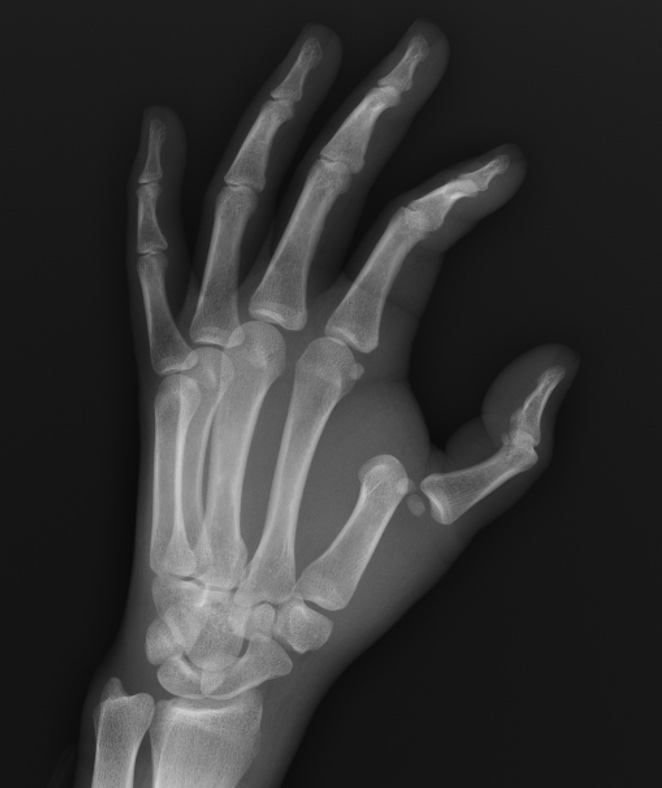

What’s the diagnosis? Gepost op 19 mei 2020 door netwerkvsseh What’s the diagnosis? @emdaily.cooperhealth.org Dit delen: Delen op X (Opent in een nieuw venster) X Share op Facebook (Opent in een nieuw venster) Facebook Delen op LinkedIn (Opent in een nieuw venster) LinkedIn E-mail een link naar een vriend (Opent in een nieuw venster) E-mail Afdrukken (Opent in een nieuw venster) Print Vind-ik-leuk Aan het laden... Gerelateerd